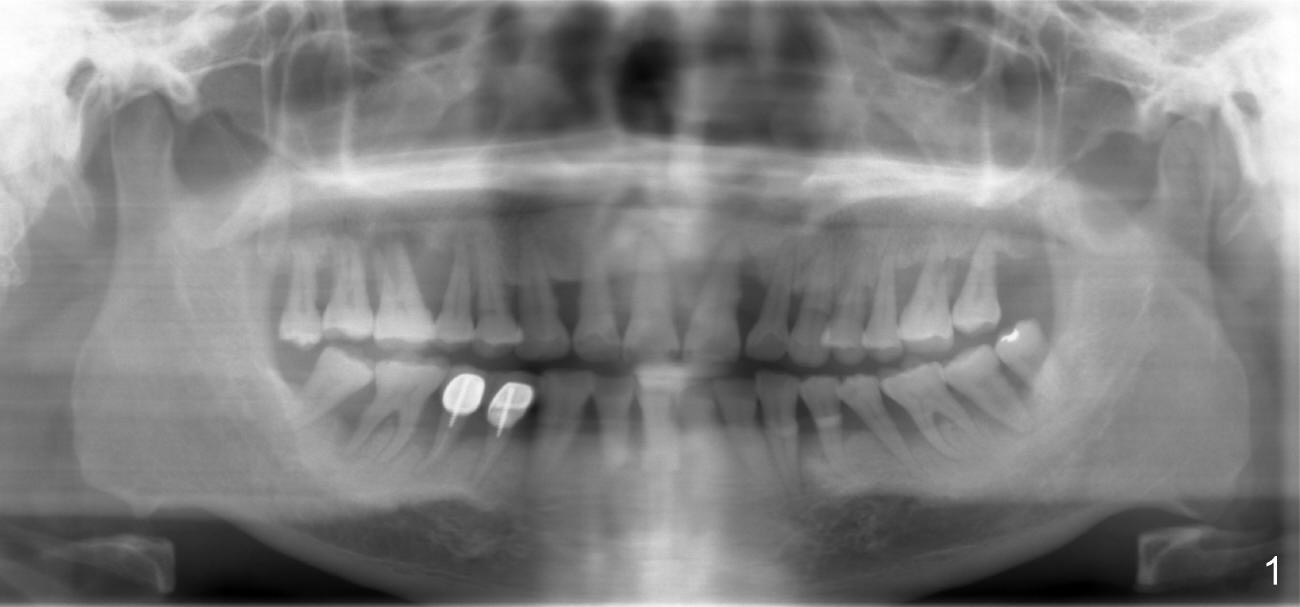

It is my pleasure to have met you in AAID meeting and have discussed one of my cases.  It tells me that good treatment planning is critical.  Can you help me deal with a case of potential bad treatment plan?  A 40-year-old man has severe periodontal disease (Fig.1).  It must be the best case for hybrid denture.  Unfortunately, three months ago, the teeth #8,9 were extracted due to mobility and replaced with immediately provisionals (Fig.2: taken 1.5 months postop).  The uniposts were permanently cemented.  Temporary crowns look long.